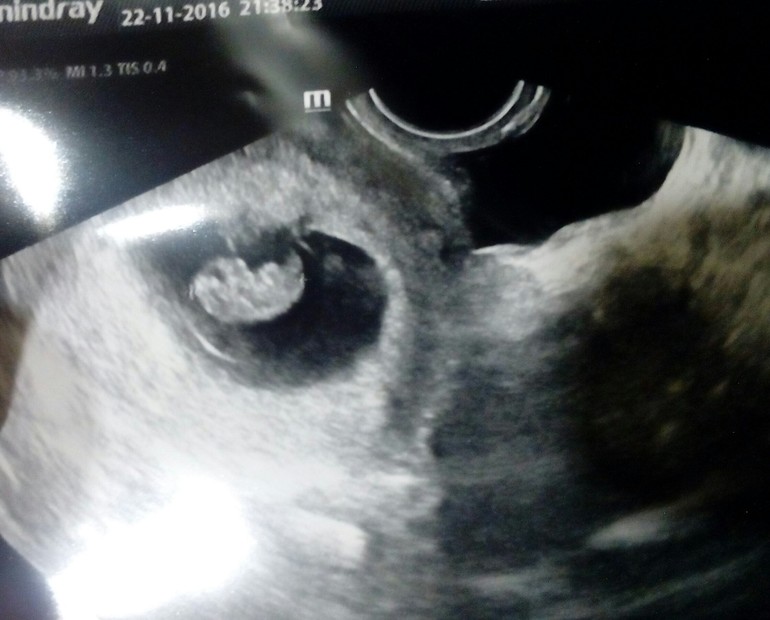

Наше первое УЗИ

Ну вот и 8 неделек

8,1 акушерские и 8,4 по УЗИ.

КТР 18 мм

Ну и фото на память